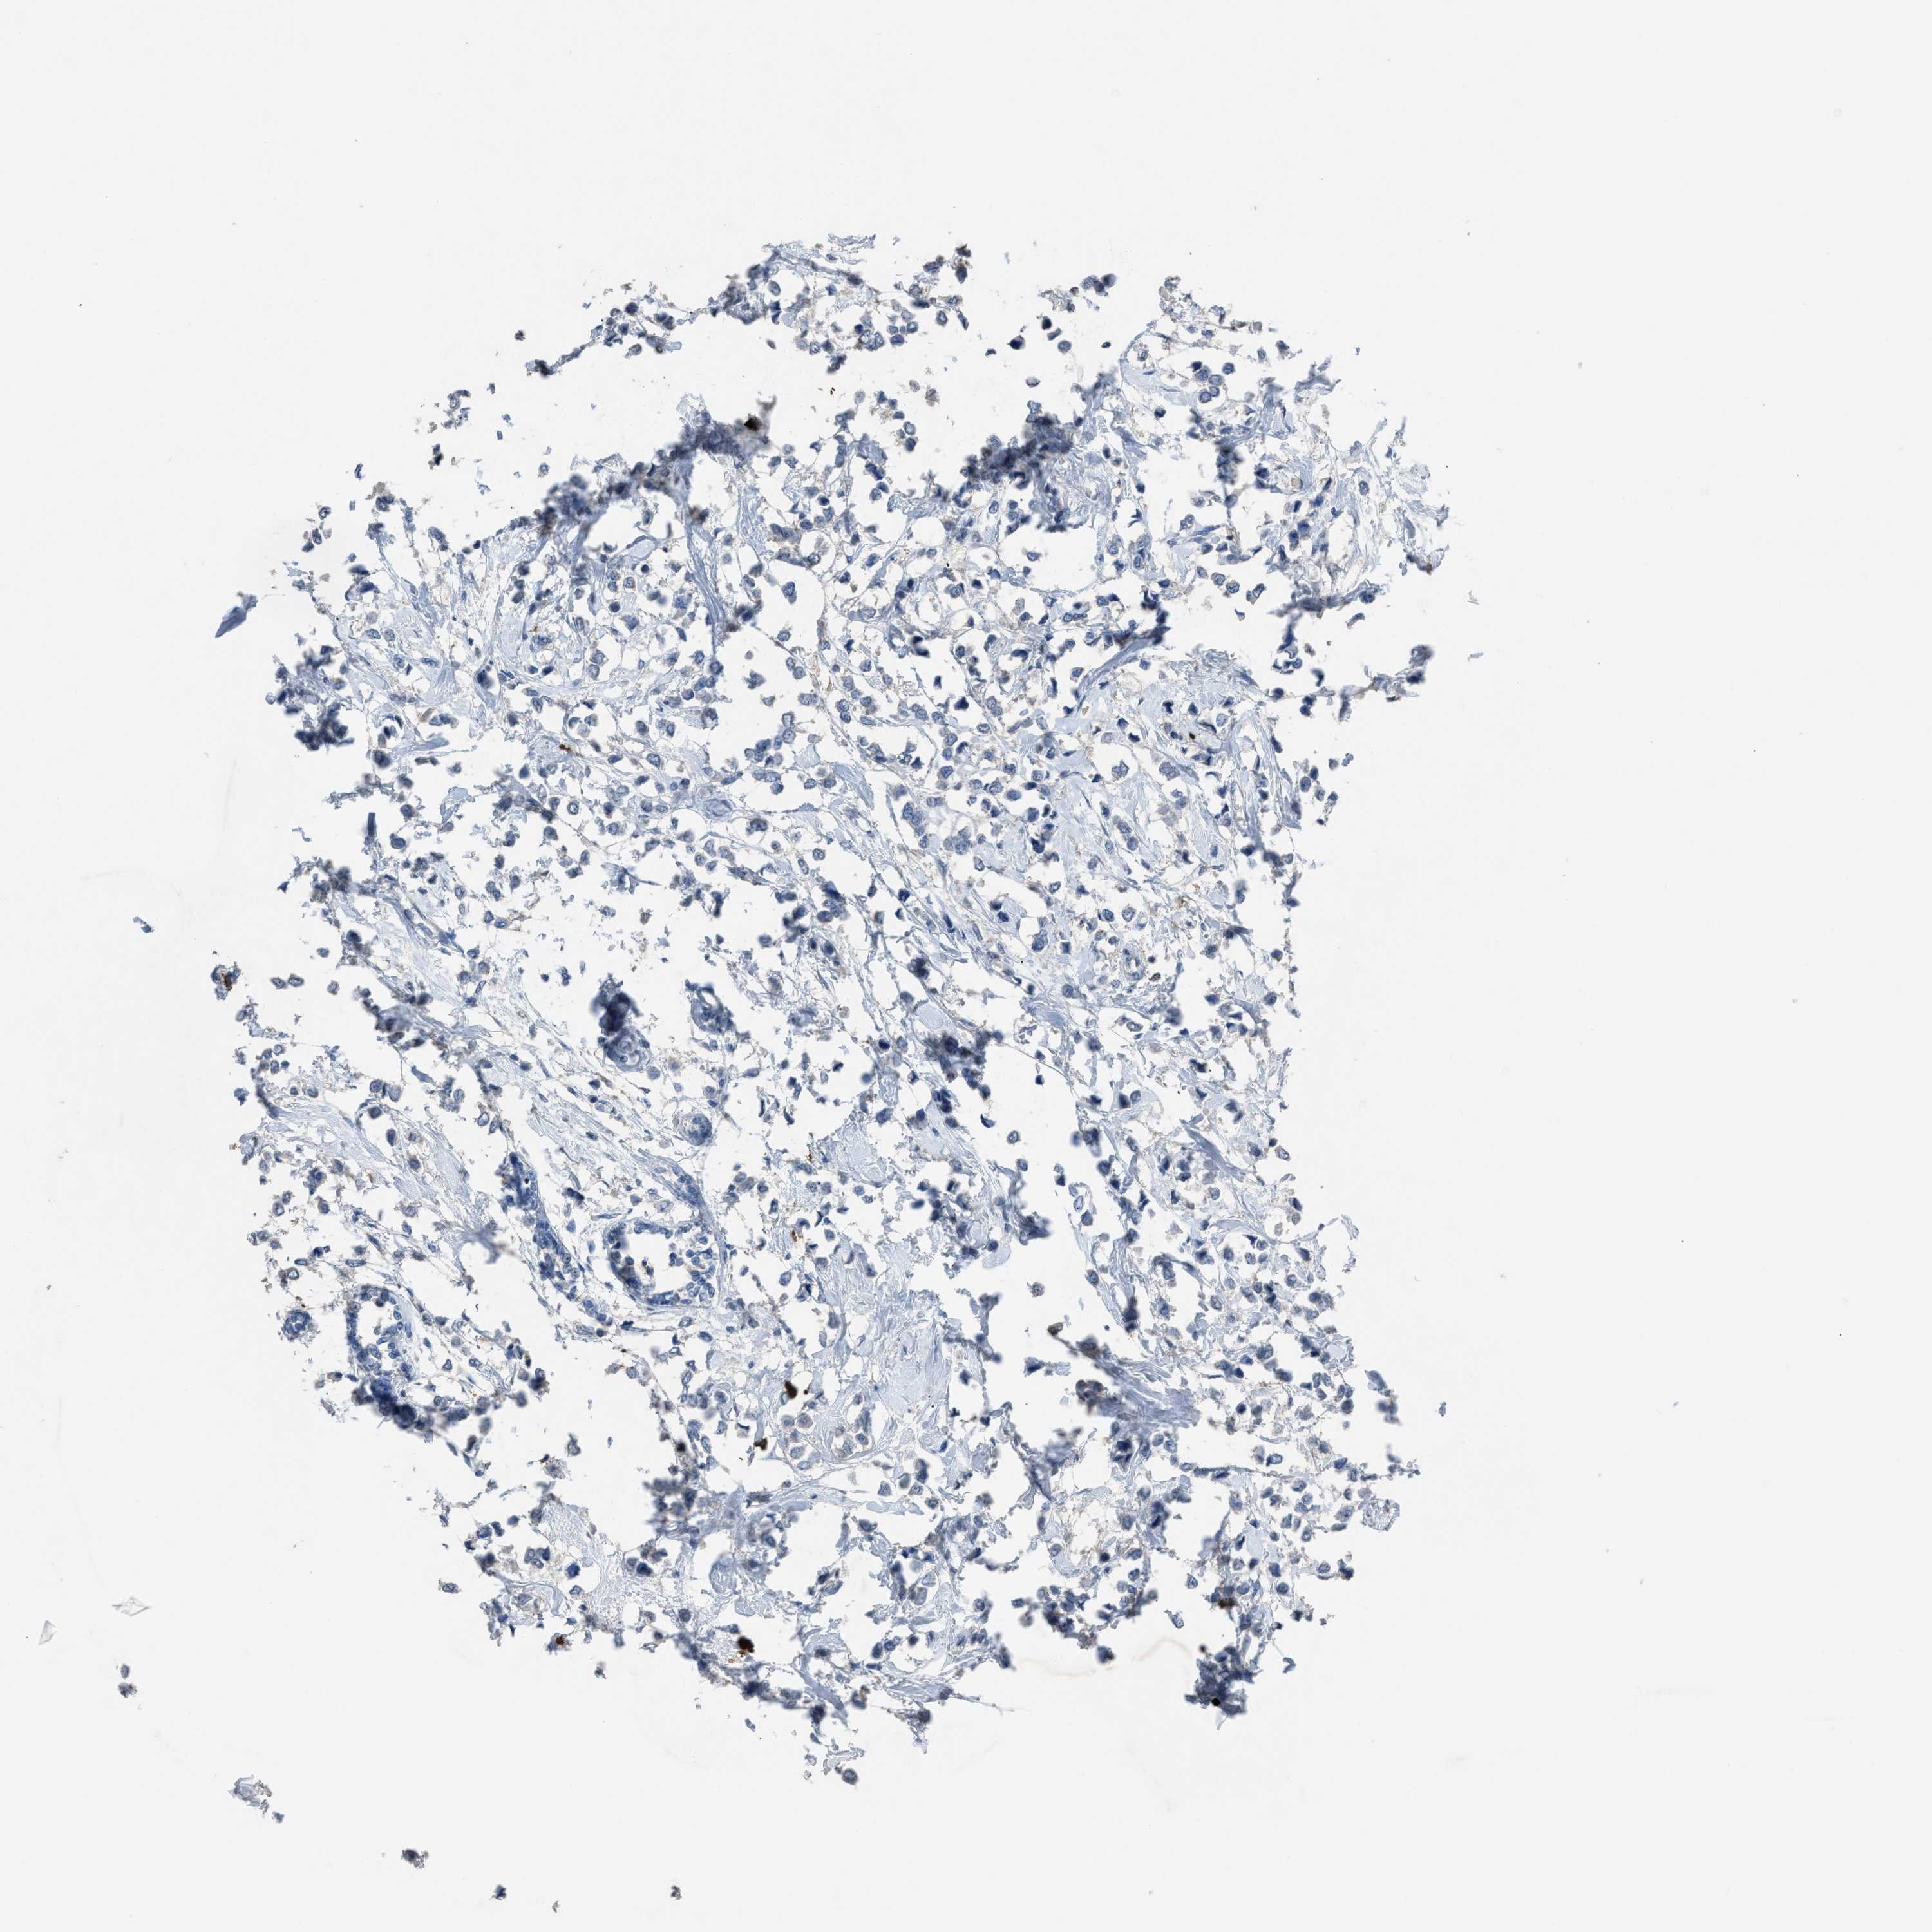

BRCA TCGA BRCA VALIDATION PROTEIN EXPRESSION

Breast cancer

Human cancer